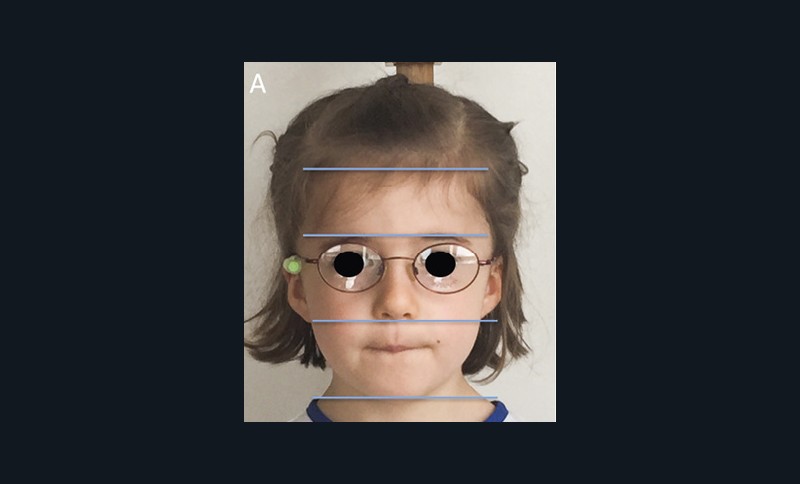

L’examen clinique orthodontique débute par un examen exobuccal de face et de profil qui permet à l’orthodontiste d’identifier certains signes d’appel du Sahos [4]. L’examen de face apprécie la forme globale du visage, la typologie et la symétrie faciale (fig. 5). Des signes caractéristiques sont souvent rapportés chez les enfants suspectés de Sahos : incompétence labiale au repos, hypotonie de la lèvre supérieure avec un angle naso-labial augmenté, visage allongé, orifices narinaires étroits et pincés et présence de cernes (fig. 6a) [5]. Ce sont des indicateurs indirects d’une obstruction ou d’un rétrécissement nasal et d’une ventilation buccale [5-6].

L’examen de profil apprécie les rapports maxillo-mandibulaires et la convexité du visage dans le sens antéropostérieur. Chez les enfants apnéiques, on note généralement la présence d’un profil convexe rétrusif avec un menton en retrait, associé à des dépôts graisseux si l’enfant est en surpoids. Une hypotonie de la lèvre supérieure, qui se traduit par un angle naso-labial ouvert, signe d’un hypo-développement maxillaire, est souvent présente [7]. Enfin, on observe parfois une contraction du muscle mentonnier associée à une occlusion labiale forcée (fig. 6b).